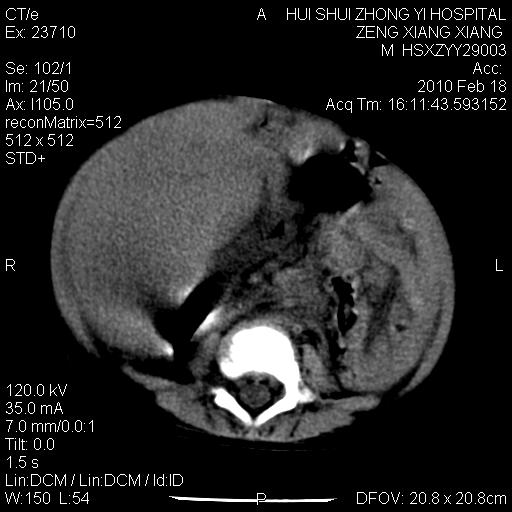

标题: PED3106:男,2岁,腹胀1月。 [打印本页]

标题: PED3106:男,2岁,腹胀1月。

定位腹膜后,肾上腺来源;

定性:恶性神经源性,肾上腺神经节母细胞瘤可能性大。

鉴别:肝母、肾母、肝脏中胚层错构瘤。

依据:年龄、有钙化,肾脏及肝脏受压移位。

肝母细胞瘤可能性大,右肾形态大体可见,不支持肾母细胞瘤,右肾移位不明显,肾上腺神经母细胞瘤可能性不大。